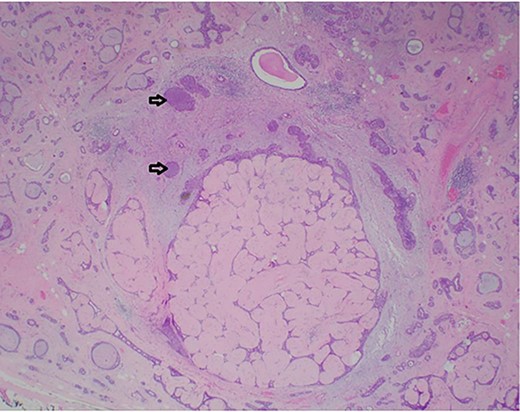

A 26-year-old female presented with a longstanding palpable fibroadenoma in the left breast. She was first investigated with ultrasound imaging showing a lobulated 2.4 × 2.5 × 1.4 cm hypoechoic lesion with well-defined margins (Fig. 1). She underwent core needle biopsy of the lesion which was histologically proven to be a fibroadenoma. There was no evidence of malignancy. She was later discharged and presented 6 years later with a history of recent enlargement of the left breast lump. Ultrasound imaging now showed increase in the size of the left breast fibroadenoma to 3.2 × 2.7 × 1.6 cm and development of an irregular outline (Fig. 2). Because of increasing size of the lesion and new indeterminate features, excision biopsy was advised. Post-excision histology revealed a 5-mm focus of classic lobular carcinoma in situ (LCIS) with a 0.6-mm area of microinvasive carcinoma within the fibroadenoma (Figs 3–6). The carcinoma was estrogen and progesterone receptor positive and Her2 negative. Atypical ductal hyperplasia was seen in the breast tissue adjoining the fibroadenoma. After presentation at our multidisciplinary tumor board, sentinel lymph node biopsy for staging of the invasive carcinoma, radiotherapy and endocrine therapy for risk and recurrence reduction, as well as genetic testing in view of her young age was discussed with the patient. Because of the small size of the invasive carcinoma, potential cost and morbidity associated with sentinel lymph node biopsy, no further surgery was performed. The patient was agreeable to proceed with radiotherapy and endocrine therapy but requested to defer genetic testing.

Photomicrograph showing a few ducts within the fibroadenoma expanded by a monotonous epithelial proliferation of classic lobular carcinoma in situ (arrows). (HE, ×20).